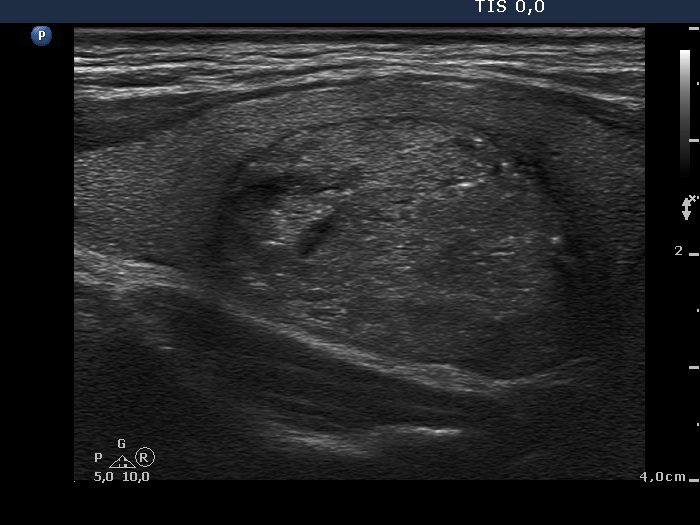

Benign hyperplastic nodule (histological diagnosis) - case 2 |

The bright granules lack the dorsal narrowing tail and there are no coexisting similarly bright lines, therefore these granules correspond to punctate echogenic foci.